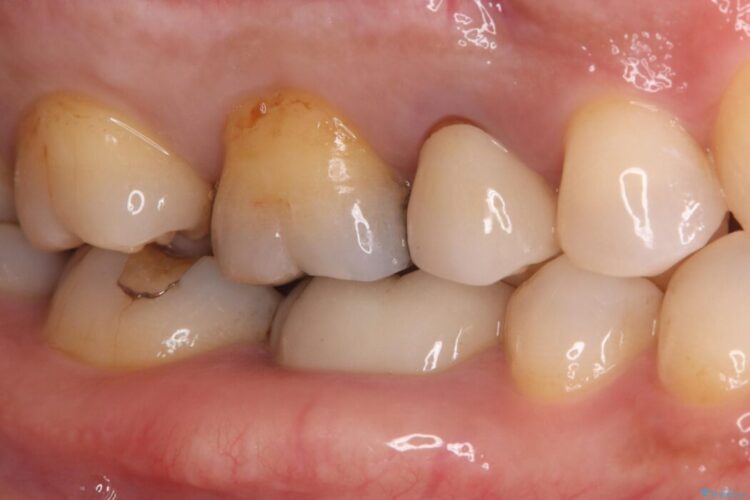

詰め物内部の虫歯治療、隠れた根管の発見

詰め物内部の虫歯治療、隠れた根管の発見 ビフォー 詰め物内部の虫歯治療、隠れた根管の発見 アフター

奥歯の詰め物が取れたとご来院された患者様です。